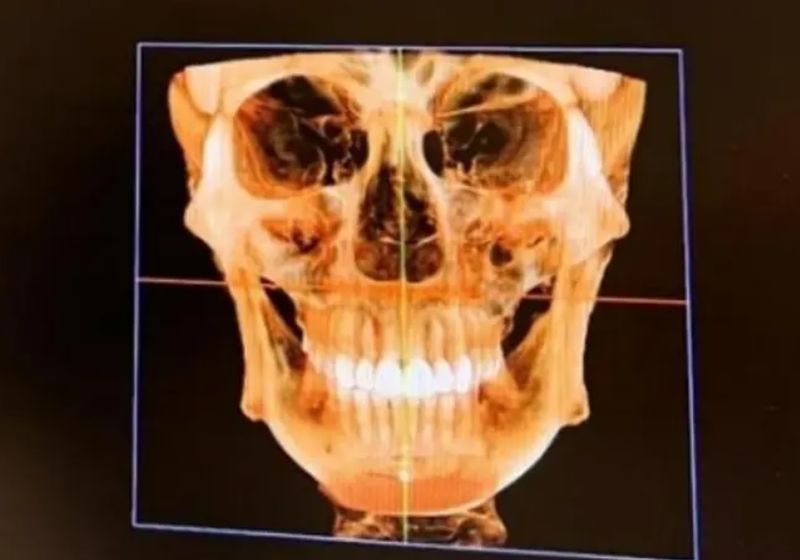

„Fața mea arată ca un puzzle!”, ar fi spus modelul în lacrimi, când a descoperit ce se află în corpul ei.

Controlul cu scanner din aeroprot ar fi semnalat prezența unui șurub chirurgical de 1 centimetru chiar sub buza de jos. Modelul crede că acel șurub a fost în corpul ei de când și-a pus o „proteză de bărbie”, în urmă cu opt ani.

„Am descoperit în mod neașteptat că am și unghii pe nas”, a mai exclamat modelul, șocată de ce a văzut că se află în corpul său.

Fang Qiyuan, în vârstă de 36 de ani, se autointitulează „fanatică a chirurgiei plastice”. Femeia are peste 19 operații plastice, între care două operații la frunte, cinci la pleoape, cinci la nas, două în bărbie și liposucție pentru repararea feței de cinci ori.